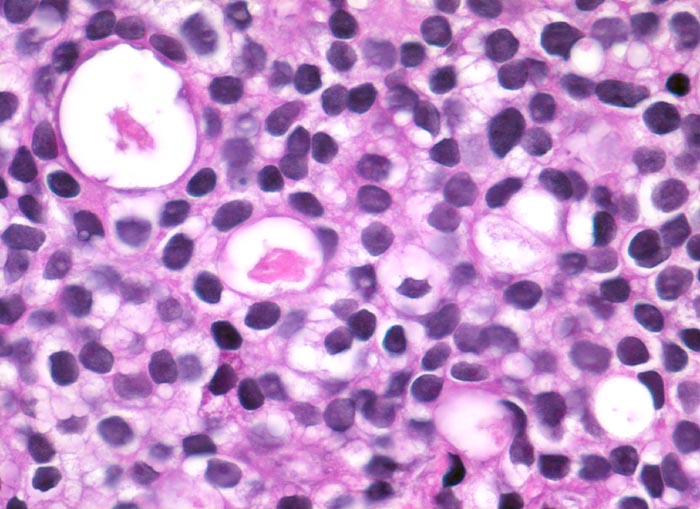

PathoPic ID 3404 - Prostatakarzinom

Prostatakarzinom

maligner Tumor

Prostata

Genitalorgane, männlich

Monomorpher kribriformer Tumor bestehend aus kleinen Tumorzellen mit rundlichen Kernen mit promimenten Nukleolen.

St.n. Bestrahlung eines Prostatakarzinoms. Jetzt Tumor in der Harnblasenwand.

Histologie

400

64

männlich